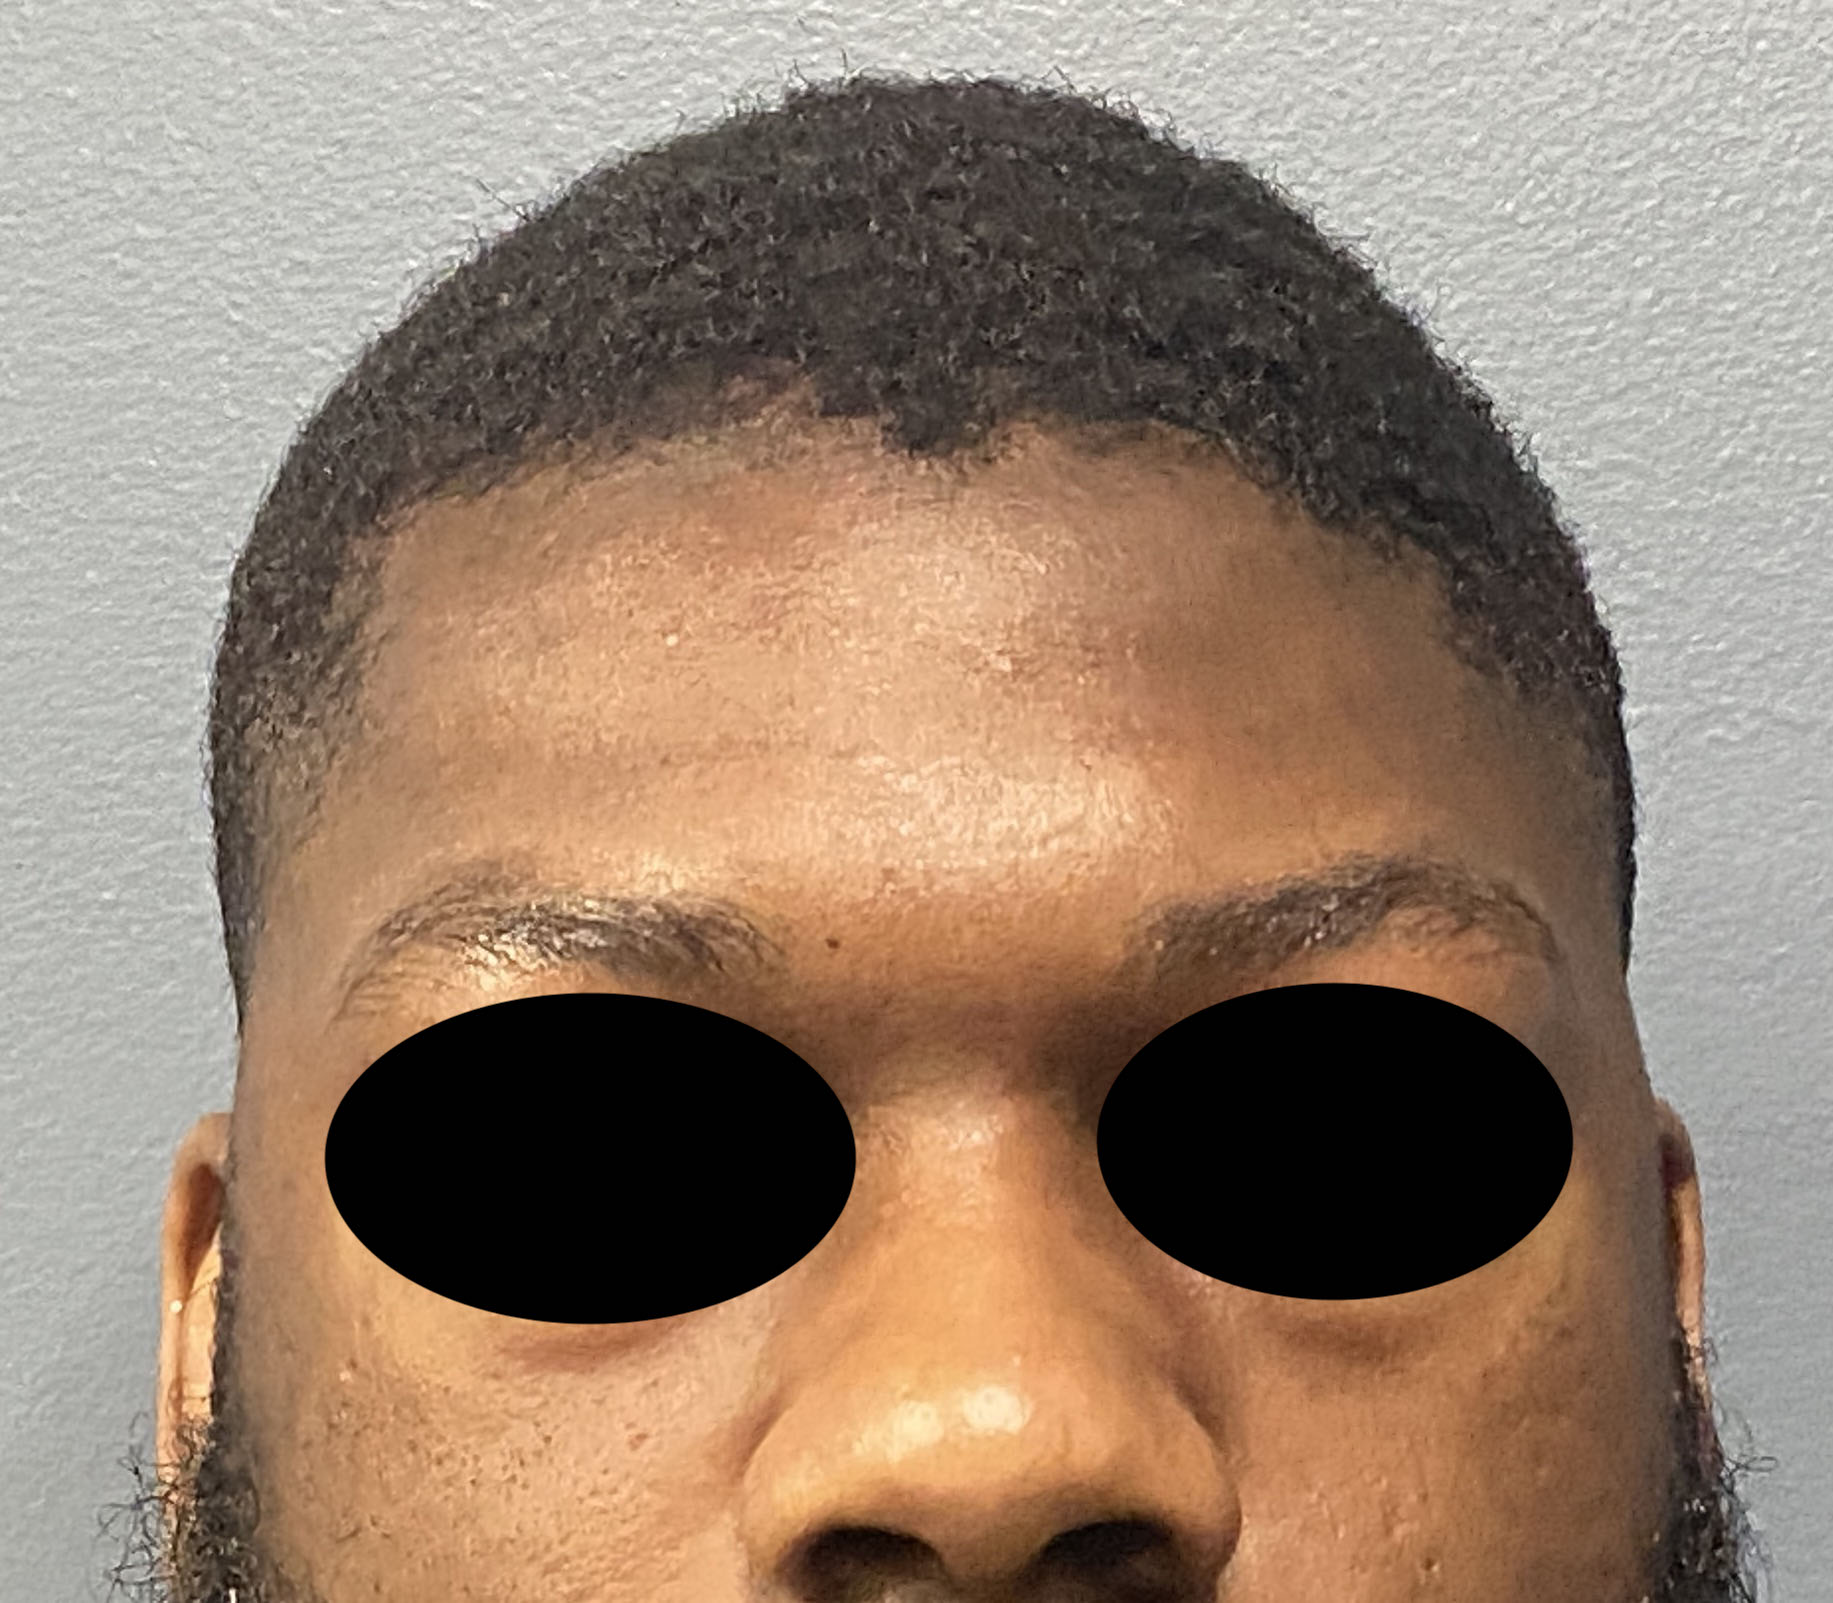

Patient 84

Desire for change of head shape from front view form an inverted V shape to a rounder and wider head shape.

Placement of custom extended forehead-temporal implants through incisions in the crease behind the ear. (he had a prior back of head skull implant which is green in the implant designs and which the head widening implants partially covered it)

Desire for change of head shape from front view form an inverted V shape to a rounder and wider head shape.

Placement of custom extended forehead-temporal implants through incisions in the crease behind the ear. (he had a prior back of head skull implant which is green in the implant designs and which the head widening implants partially covered it)